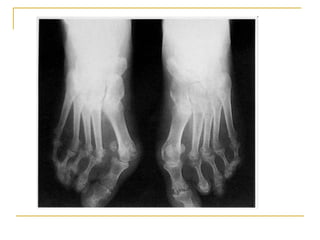

Pieds :

Arthrite + luxation des MTP = avant-pieds ronds

Hallux valgus + quintus varus + orteils en griffe = avant-pieds triangulaires

Affaissement de la voûte plantaire = pieds plats

Radiographie standard :

les signes caractéristiques de la PR sont rarement visibles

avant 6 mois d’évolution

-un épaississement des parties molles,

-une augmentation de la transparence radiologique

épiphysaire, l’« ostéoporose en bande »

-érosions périarticulaires, puis

-des géodes intraosseuses juxta-articulaires caractéristiques

et secondairement

-le pincement de l’interligne articulaire